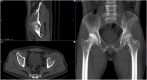

Introduction: and importance: Pelvic osteosarcoma is quite rare and is a challenging task for orthopedic surgeons. This aim of this study is to present the first case report using customized 3D-printed prosthesis in Vietnam.

Case presentation: 57-year-old male was diagnosed with pelvic osteosarcoma. After neoadjuvant chemotherapy, we did limb-salvage surgery after partial pelvic resection. He had to undergo another surgery due to an infection complication that exposed part of the prosthesis. At 6 months follow-up, the patient's overall status was stable. VAS score when moving is 2/10. He can walk with one crutch. Patient is still being followed up and treated.